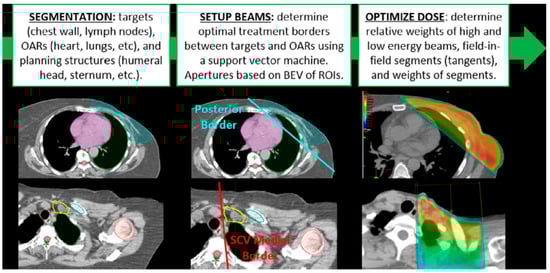

Figure 1.

A typical automation workflow starts with automated segmentation of targets and organs at risk (OARs), followed by treatment planning (here described by beam setup and dose optimization). The individual tasks may be automated separately or a complete end-to-end process with no user intervention until the end. This example is from Kisling et al. [1].